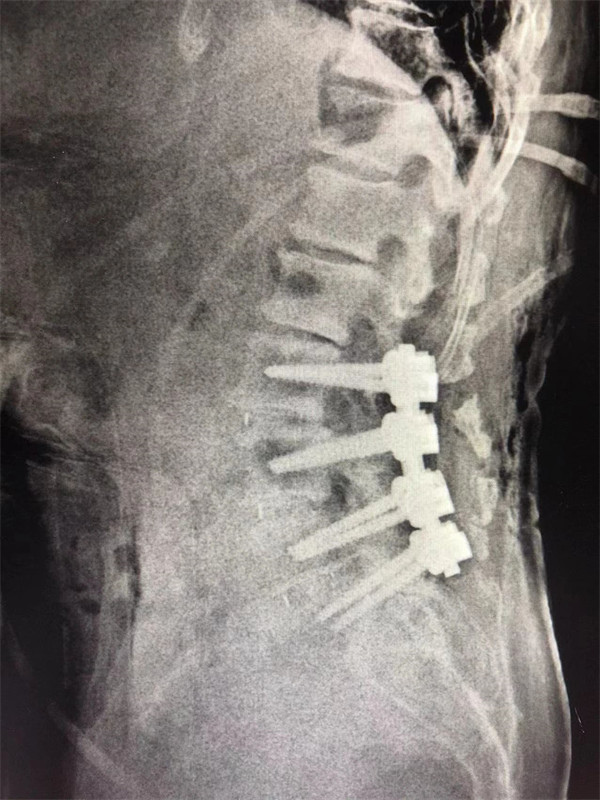

手術后↓

戈才華主任團隊討論病情及手術風險,并與麻醉科醫(yī)生多次討論術中麻醉風險,經(jīng)過詳盡周密的布置之后,最終給阿婆在全麻下進行腰3/4,4/5,腰5/骶1腰椎椎體間融合術。

術后阿婆腰痛伴雙下肢疼痛明顯緩解,術前疼得晚上睡不著覺的情況不再出現(xiàn)。阿婆和家屬連聲道謝,對醫(yī)生的治療技術和服務贊不絕口。